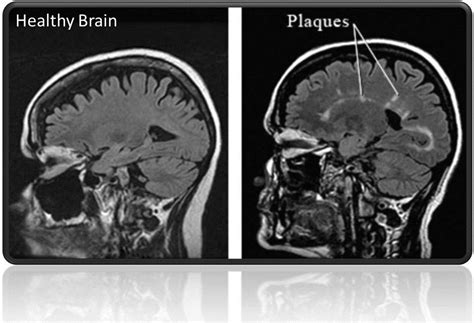

Lea Johnson Blog